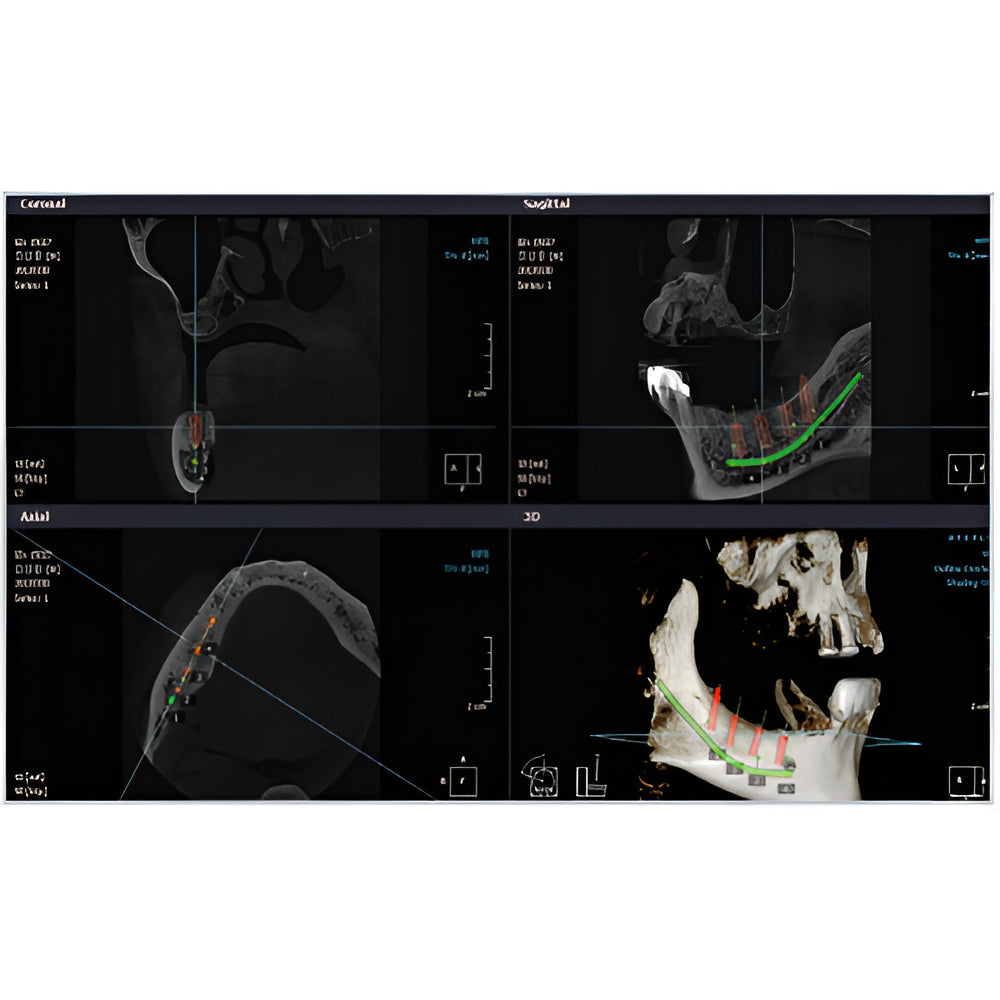

Rayscan Alpha brings another innovative technology with less Recon time and bigger FOV Size. And there are also new features – Fast scan mode, Object scan and Multi FOV.

- 2D/3D Imaging Software with License

- Multiple Scan Modes